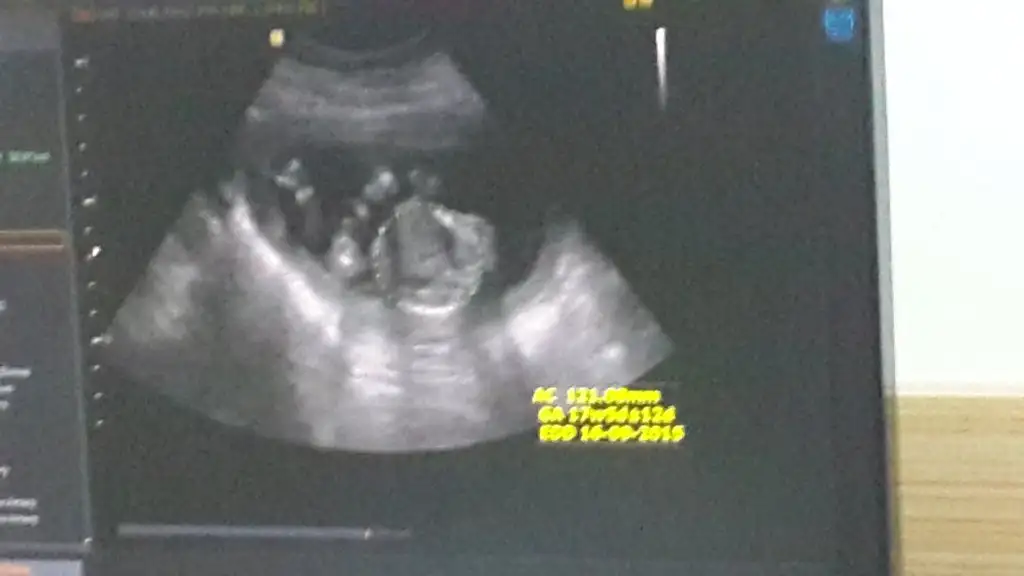

Kızlar bu bebişede bi yorum yaparmısınız arkadaşımın ama doktor büyük ihtimal kız dedi ama bide siz bakın bacak arası resmide var

Eklentiler

• 20150413_102628.webp

20150413_102628.webp

22,4 KB · Görüntüleme: 123

• 20150413_102513.webp

20150413_102513.webp

14,8 KB · Görüntüleme: 127